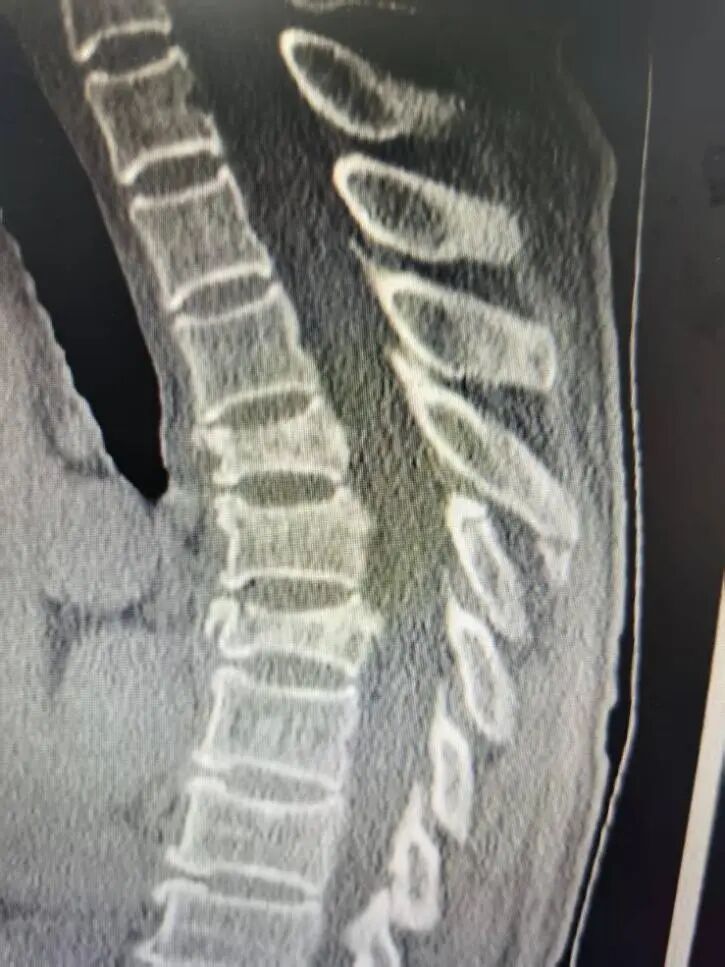

签约仪式后,朱卉敏教授团队立即开展手术演示。手术针对一名多发胸椎椎体骨折患者。一直以来,胸椎尤其是高位胸椎手术因解剖结构复杂、毗邻脊髓与大血管,稍有不慎,极易损伤神经导致瘫痪,容错率几乎为零,向来是脊柱外科的“禁区”与难点,令无数医师畏之如虎、知难而退。

朱卉敏教授团队一边操作,一边为现场观摩的福鼎市医院骨科团队详细讲解解剖标志、操作要点与风险规避技巧。手术过程流畅、视野清晰、出血极少,历时约50分钟,手术顺利完成。术后患者即刻苏醒,次日即可下床活动,疗效显著获得在场医护人员与患者家属的高度赞誉。